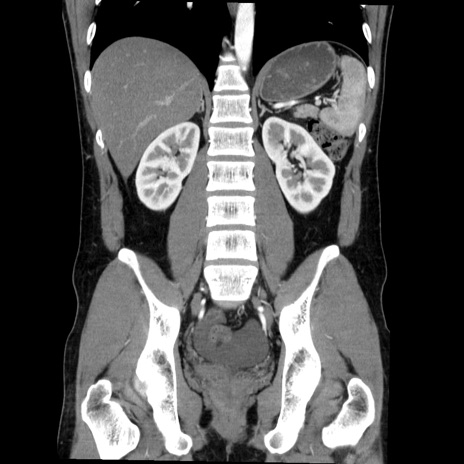

症例36(冠状断像)

【症例】20歳代 男性

【主訴】心窩部痛

【現病歴】今朝より上腹部痛あり。一旦軽快していたが再度出現したため救急要請。昨日夕に白身の魚を含む刺身を食べた。

【身体所見】BP 136/89mmHg、HR 74/min、BT 37.0℃、腹部:膨満、軟、心窩部に圧痛あり。反跳痛なし、筋性防御なし、腸雑音やや亢進あり。

【データ】WBC 17700、CRP 0.48